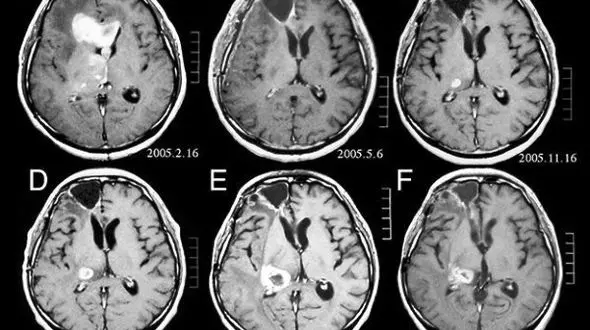

رکنا: محققان دریافتند انجام سی تی اسکن رشد تومورهای مغزی را افزایش می دهد.